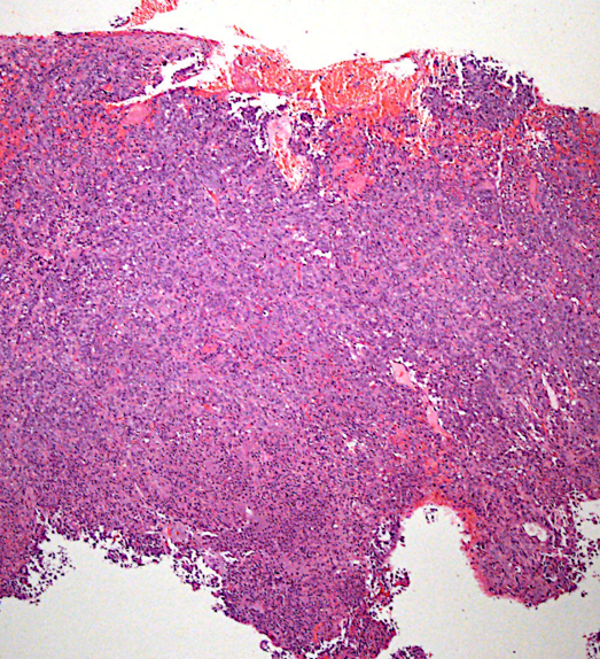

Recent cases